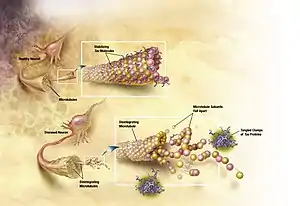

AD is also considered a tauopathy due to abnormal aggregation of the tau protein. Every neuron has a cytoskeleton, an internal support structure partly made up of structures called microtubules. These microtubules act like tracks, guiding nutrients and molecules from the body of the cell to the ends of the axon and back. A protein called tau stabilises the microtubules when phosphorylated, and is therefore called a microtubule-associated protein. In AD, tau undergoes chemical changes, becoming hyperphosphorylated; it then begins to pair with other threads, creating neurofibrillary tangles and disintegrating the neuron's transport system.[105] Pathogenic tau can also cause neuronal death through transposable element dysregulation.[106]